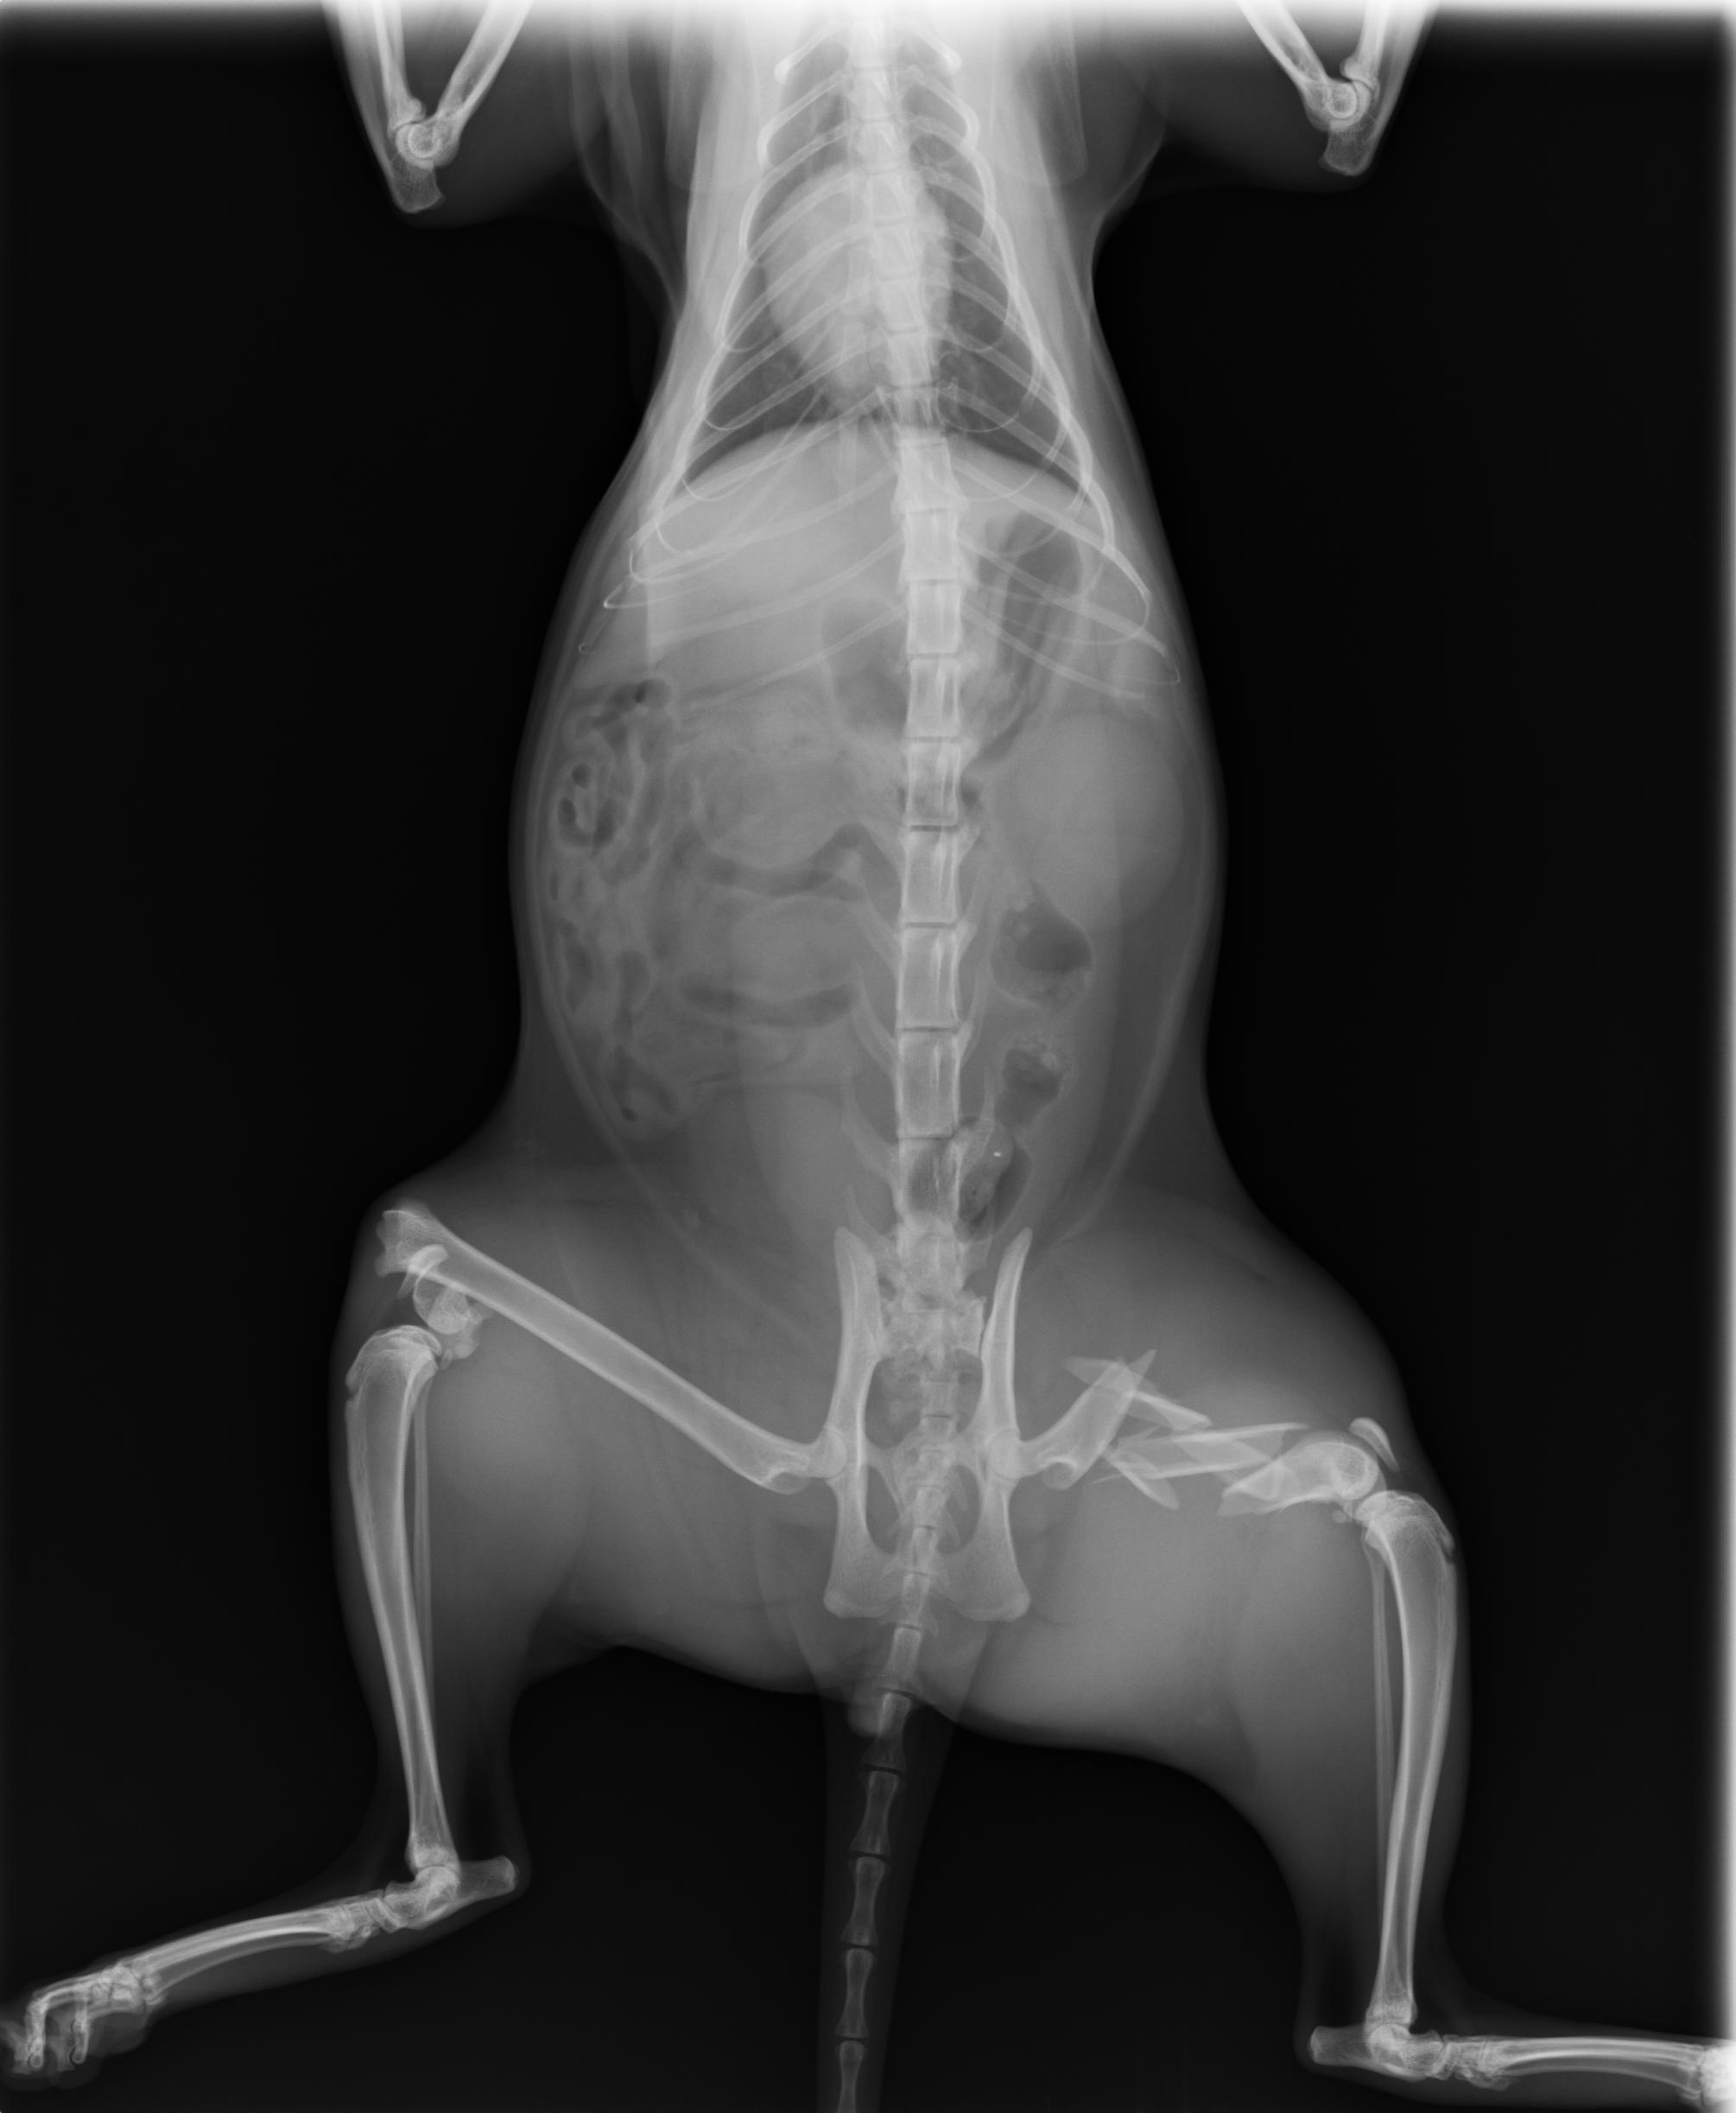

主題: 車禍後左腳粉碎性骨折及後右腳骨折 申請者姓名: 許桂菱 花色: 申請日期: 2013-04-01 00:14:01 申請者部落格: 申請者臉書網址: 所在縣市/合作醫院: 台中市/春天動物醫院 治療費用: 25100元 需求人數: 26人 已結案 (2013-06-27 14:19:18) 報名人員: 小娃(已付款)、nini(已付款)、陳嘉芸(已付款)、Hui Mei Chen(已付款)、Ann Cat(已付款)、蔡秀芳(已付款)、高小玉(已付款)、Irene Chu(已付款)、Huei Wen Chuang(已付款)、Maureen Huang(已付款)、Winnie Chen(已付款)、chiawei(已付款)、May Ho(已付款)、潘逸群(已付款)、BonnieL(已付款)、Richie Hsu、Chenyu Chang(已付款)、Richie Hsu、Yuki Natumei(已付款)、Ou Han x2(已付款)、Kiki Liang(已付款)、Ching-fang Shaw(已付款)、Cathy Chang(已付款)、胡嘟嘟(已付款)、胡嘟嘟(已付款)、Claire Hoi(已付款)、Judy媽(已付款)、 候補人員: 動物病情說明: 原在鹿港市場的大有街且已TNR之公浪貓,因車禍造成後左腳粉碎性骨折及後右腳骨折而無法行走!醫院先進行右腳骨折手術,於一星期後進行左腳粉碎性骨折的拼接手術,右腳於兩星期恢復良好且能行走,但貓咪雖受傷對左腳傷口卻想盡辦法去舔開,造成傷口癒合時間拉長,經過一個月後,左腳傷口癒合情況良好!

動物近況說明: 左腳因施力仍會疼痛,目前暫時在鹿港大有街原生長地之居民空屋休養中途,並進行送養中!